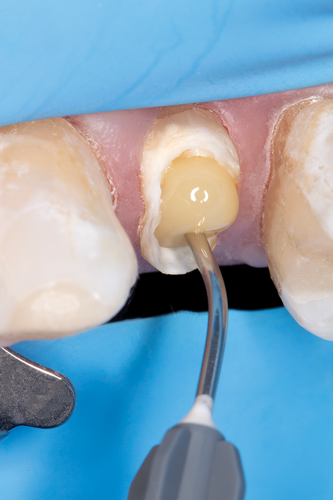

Fig 15. Flowable resin composite injected into the post channel using an angled tip.

Figure 15

Fig 16. Fiber post inserted into the post space to the base of the prepared channel.

Figure 16